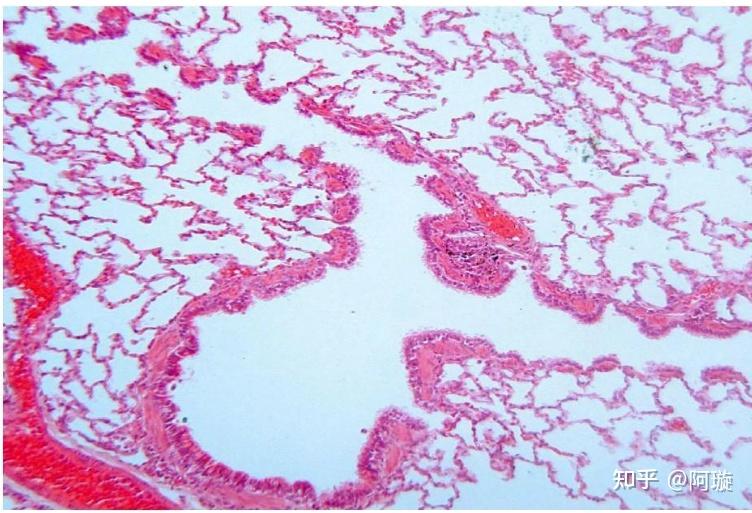

人肺终末细支气管

在正常肺组织中,支气管树逐级分支,终末细支气管分出以后,肺泡自呼吸

呼吸性细支气管→…→肺泡.